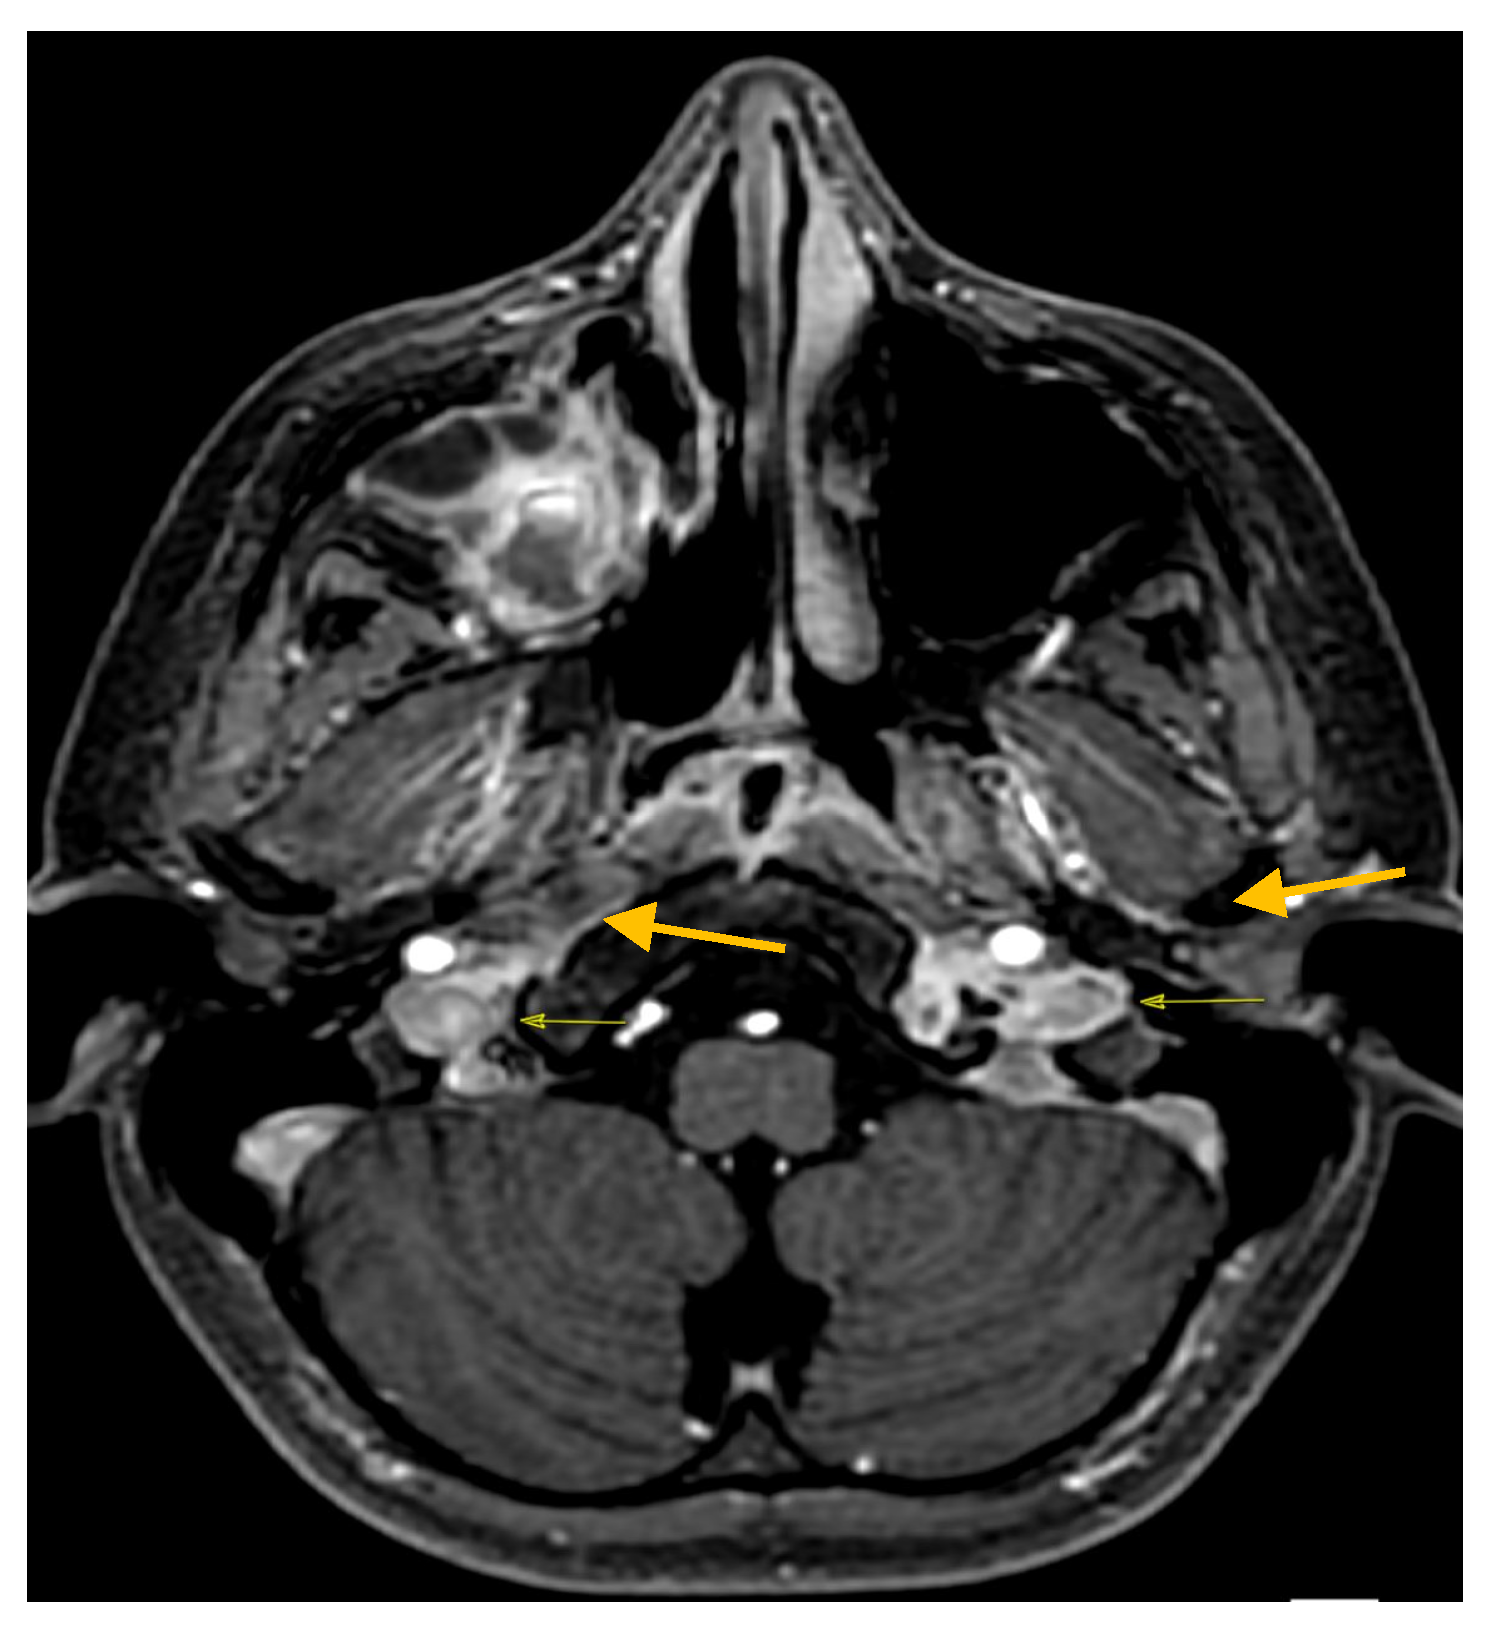

2. Case Report

| Colomba C. et al./Italy/2023 | 12 y | M | No | No | sinus drainage material | sinusitis, meningitis, CSVT | ceftriaxone + vancomycin + metronidazole → cefotaxime | healed |